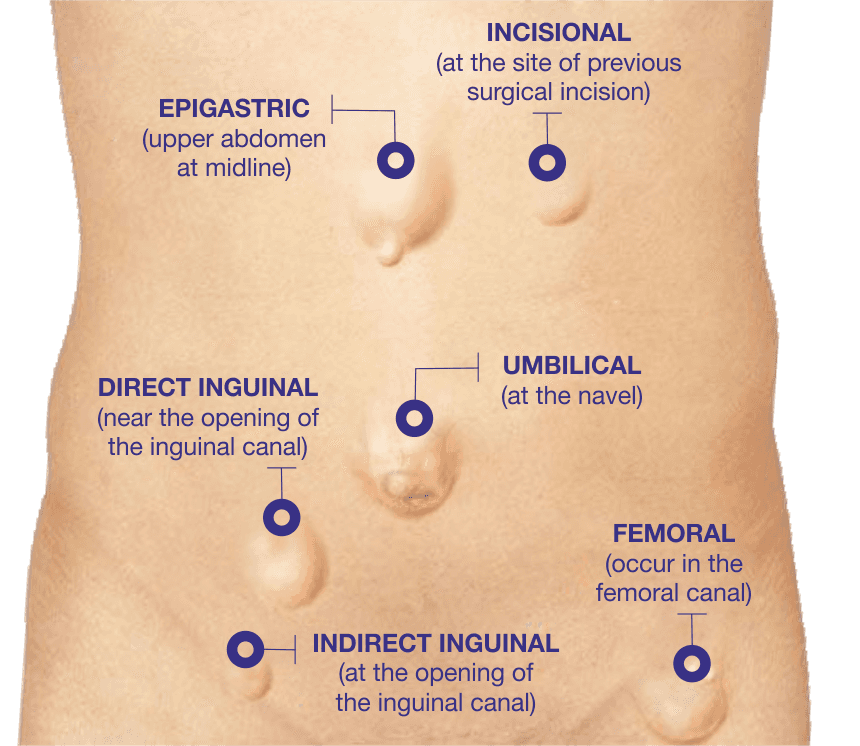

Best Hospital for Robotic Hernia Surgery in Hyderabad : Pace Hospitals

Groin pain in athletes | The BMJ

Abdominal and Pelvic Pain in the Nonpregnant Female | Tintinalli’s …

Female Abdominal Pain | Types | Symptoms | Causes | Diagnosis | Treatment

What Is Pain In Lower Right Side Of Stomach – StomachGuide.net